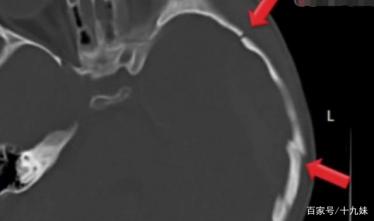

结果很快出来了,医生一看不得了,这个6岁的小女孩竟然出现了脑出血,长度约2cm,出血量约20ml,更为致命的是,小孩的颅骨还有两处裂痕。事不宜迟,医院赶紧联系医生和专家进行了会诊。